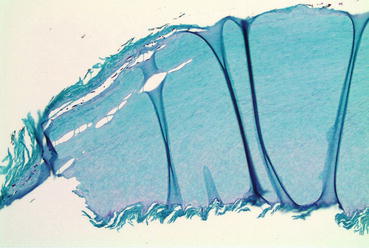

Fig. 4.6

Deep SWO: pathology shows fungal elements in the superficial and mid-nail plate

Diagnostic Clues

It is important to conduct mycological studies, in order to appropriately diagnose and treat onychomycosis [10]. Diagnosing SWO may be performed using direct microscopy with 40 % potassium hydroxide (KOH) mounts, fungal cultures, and nail clippings with periodic acid-Schiff (PAS) staining for histologic analysis (Fig. 4.11) [7, 12]. In some cases of SWO, taking a clipping might be difficult, as the infection is often located in the central part of the nail plate without involvement of the distal nail. Scraping of the superficial nail plate is the best way to obtain samples for KOH and culture. Of note, potassium hydroxide microscopy and culture carry a relatively low negative predictive value (<60 %) and, therefore, warrant repeat testing in patients with possible SWO that initially test negative [12].